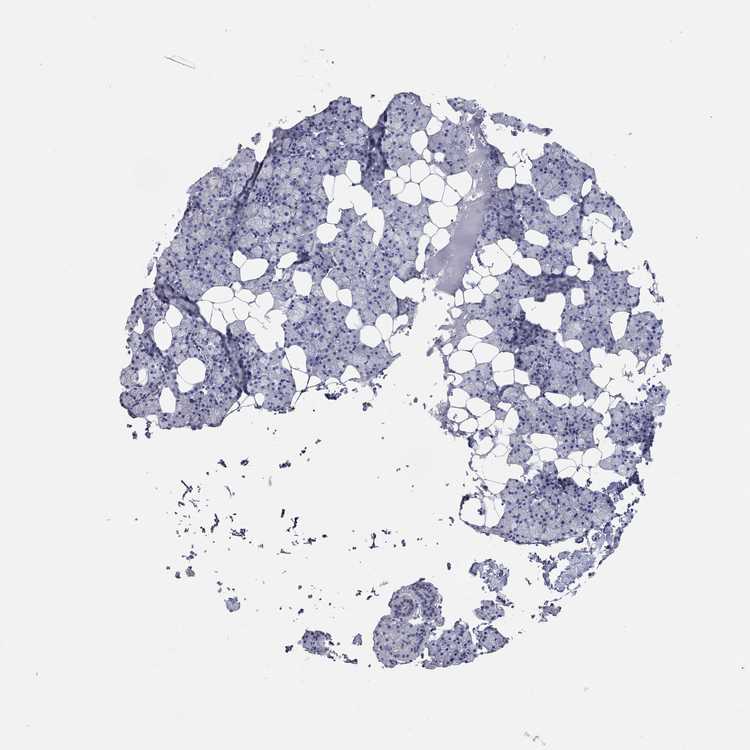

SALIVARY GLAND - Antibody stainingi

Antibody staining in the annotated cell types in the current human tissue is reported as not detected, low, medium, or high, based on conventional immunohistochemistry profiling in selected tissues. This score is based on the combination of the staining intensity and fraction of stained cells.

Each image is clickable and will lead to virtual microscopy that enables deeper exploration of all samples and also displays staining intensity scores, fraction scores and subcellular localization as well as patient and tissue information for each sample.

Antibody HPA040199Antibody HPA040215

Glandular cells Not detectedNot detected